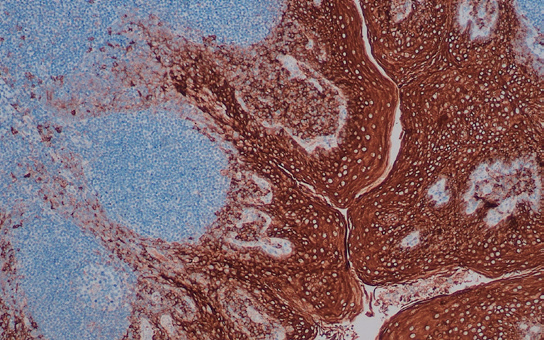

EMA  是一种分子量为400kDa 的跨膜糖蛋白,广泛分布于上皮细胞及 其来源的肿瘤。该抗体可标记大部分正常上皮及其来源的肿瘤,在95%的 大细胞间变性淋巴瘤中也呈阳性表达。EMA  可用于鉴别:间皮瘤与腺癌;皮 肤鳞状细胞癌与基底细胞癌; ALK 阳性的大细胞间变性淋巴瘤与其他类型 淋巴瘤。

扁桃体鳞状上皮EMA 表达

用EMA(HD010C03)染色

胞膜/胞浆阳性

DAB显色